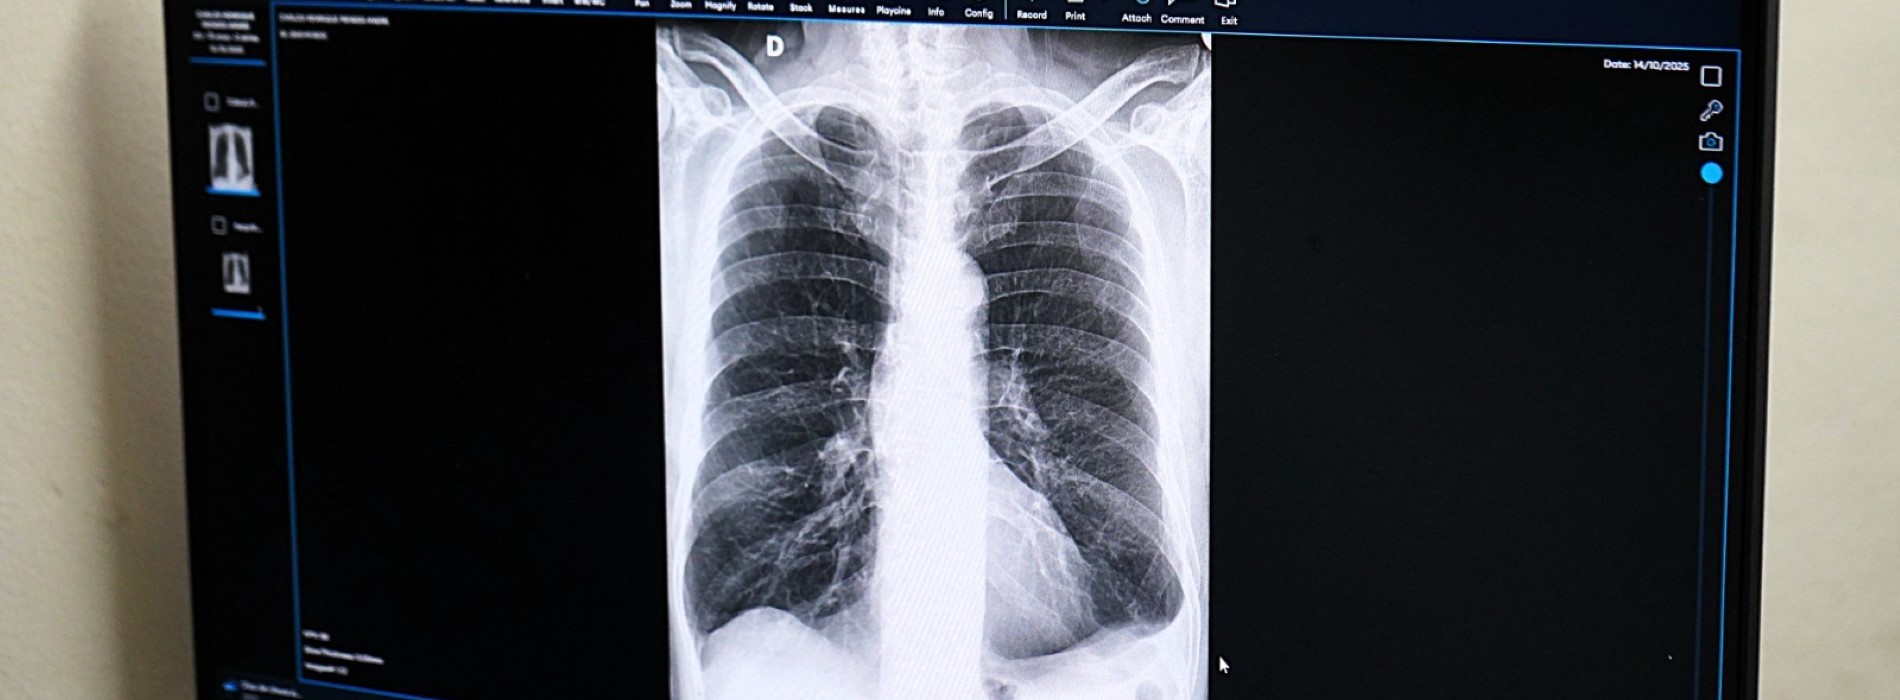

A tecnologia está presente nos hospitais São João Batista (HSJB) e Dr. Munir Rafful (HMMR), Dr. Nelson dos Santos Gonçalves (HNSG) e na UPA (Unidade de Pronto Atendimento) Santo Agostinho, atuando no suporte à análise de exames de radiografia, especialmente em contextos de urgência e emergência. Na prática, a IA funciona como uma segunda opinião diagnóstica.

Os exames seguem o fluxo normal das unidades de saúde e são automaticamente enviados para análise da ferramenta, que retorna em até cinco minutos com o diagnóstico que auxilia os médicos na tomada de decisão. O processo ocorre sem a necessidade de alterações na infraestrutura existente.

A tecnologia permite, ainda, a classificação automática dos exames por nível de prioridade – baixa, moderada e alta – contribuindo para a organização da fila de atendimento, conforme a gravidade dos casos. Até o momento, 44% dos exames analisados foram considerados normais, 31% classificados como de prioridade moderada e 25% como de alta prioridade.